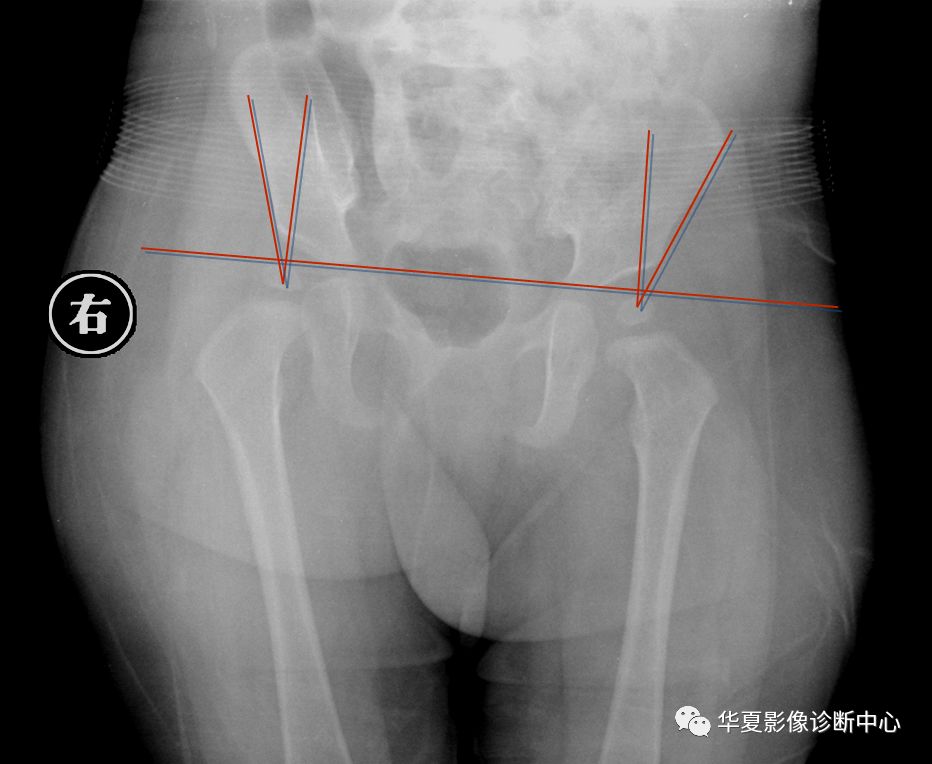

1.Von-Rosen (外展内旋位)摄片法

婴儿仰卧位,双下肢外展45度,尽力内旋位摄片。

正常时骨干轴线向上的延长线经髋臼外缘相交于腰5与骶1的平面以下。但脱位时此线经髂前上棘相交于腰5骶1平面以上。